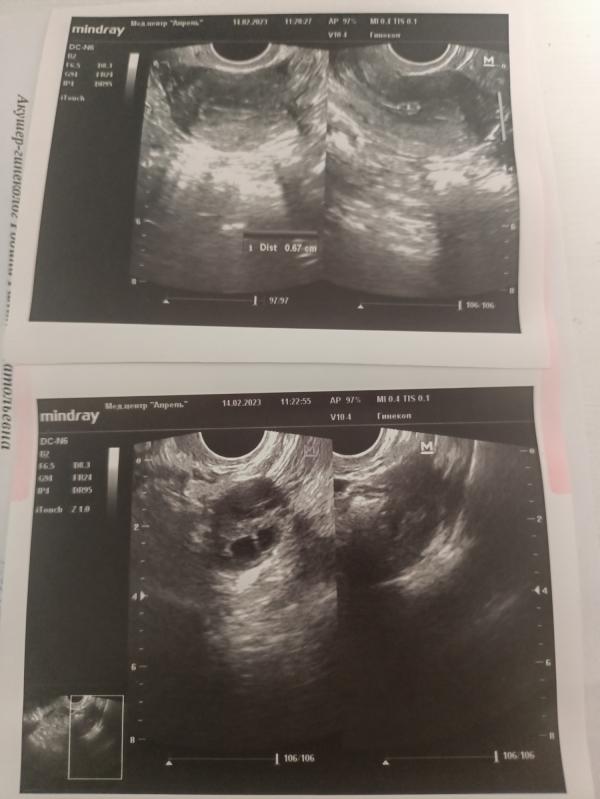

Вот узи.

Девочки,такая ситуация. Неделю назад сходила на УЗИ полип эндометрия был 6 мм, сегодня сходила на УЗИ полип уже 8мм. Может он так быстро расти?